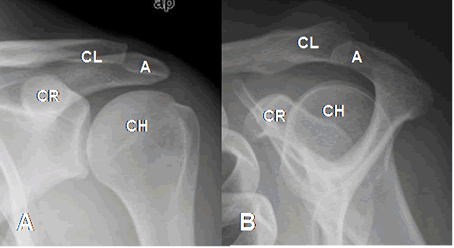

Estructuras óseas a tener en cuenta: Cabeza del húmero, glenoides, apófisis coracoides, acromión y clavícula distal. (Fig 7).

Fig 7. Estructuras del hombro.

A: Rx AP y B: Rx outlet. CH: Cabeza del húmero. CL: Clavícula distal. A: Acromión. CR: Coracoides.